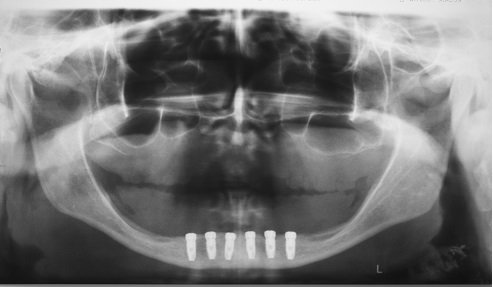

Abaixo, trago pra vocês um caso clínico isolado que faz parte de uma pesquisa que estamos desenvolvendo na USP-Fundecto, onde implantes tradicionais sem grandes alterações de desenho e superfície, colocados há mais de cinco anos, vêm sendo avaliados clínica e radiograficamente. Os resultados iniciais têm sido promissores, mostrando altos índices de sucesso com resoluções protético-cirúrgicas bastante simples.

Este caso resume bem o conteúdo do texto desta semana. Quando temos situações favoráveis e utilizamos implantes e técnicas consagradas, a possibilidade de sucesso em longo prazo é muito grande, principalmente porque estamos replicando aquilo que já foi exaustivamente comprovado na literatura científica.

Figura 1 – Radiografia panorâmica imediatamente após a colocação dos implantes. Observar a boa disponibilidade óssea e a excelente disposição dos implantes